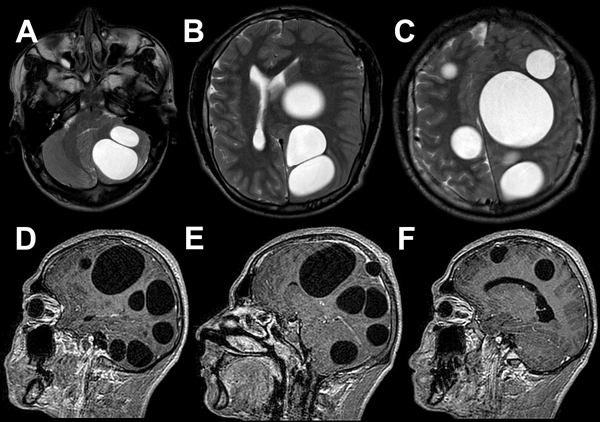

Para mejor valoración de las lesiones cerebrales, se solicitó resonancia magnética cerebral con contraste que informó: a nivel supratentorial, en secuencia T2 y FLAIR, múltiples imágenes quísticas de gran tamaño, la mayor de ellas a nivel frontoparietal izquierdo de aproximadamente 100 ml con discreta desviación de línea media, gran efecto de masa y colapso ventricular. Posterior a esta última se observaron otras dos lesiones de voluminoso tamaño; a nivel infratentorial se evidenciaron dos lesiones de similares características con importante efecto de masa (Figura 2).

Figura 2. A-C) RM T2 axial preoperatoria, se evidencian múltiples quistes hiperintensos en hemisferio cerebeloso izquierdo y ambos hemisferios cerebrales. D-F) RM T1 con contraste sagital preoperatorias, se observan las mismas lesiones que en secuencia anterior sin realce de contraste.